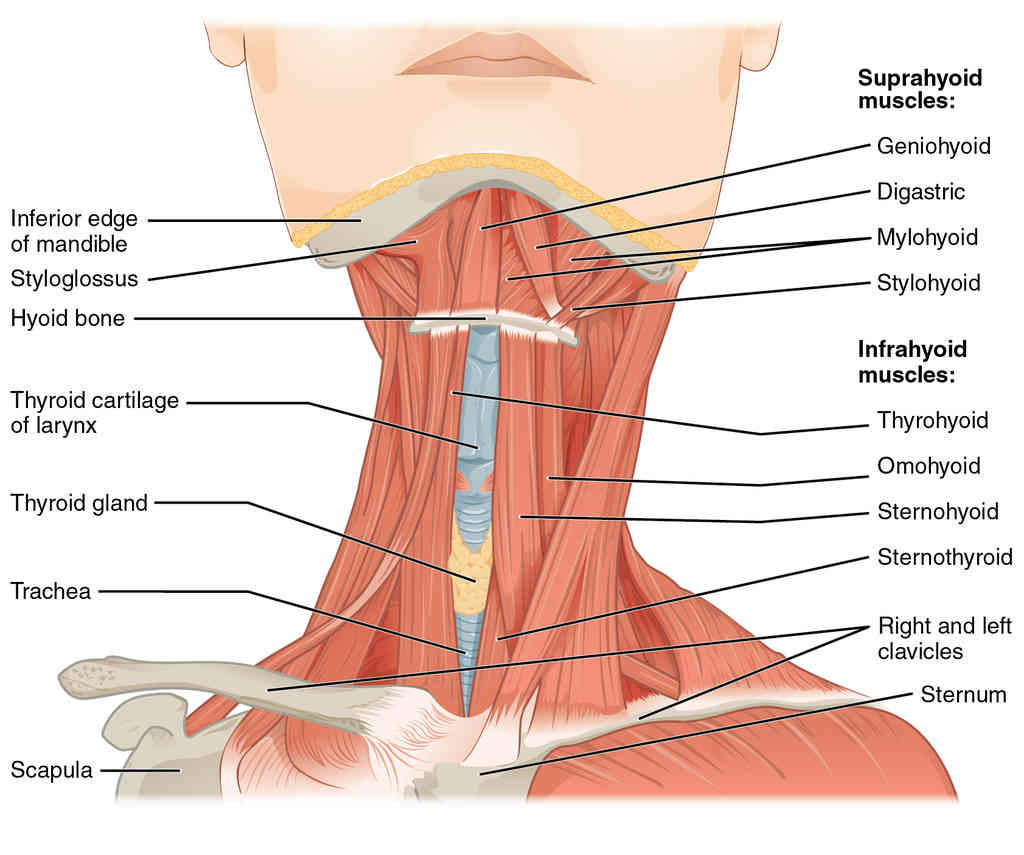

This page is under construction. For now, it is just a resource of the images found in the OpenStax Anatomy and Physiology Handbook. It wil slowly change into a revision tool. Each slide has a number. Use this to refer to the slide. When completed, it will have an unlabelled section, with labelled slides in parallel. On the unlabelled slides, write your answer and use the labelled slide to assess yourself. Keep track by also noting the number on each slide. Improvement at each attempt is important, more so than full marks on a first attempt.